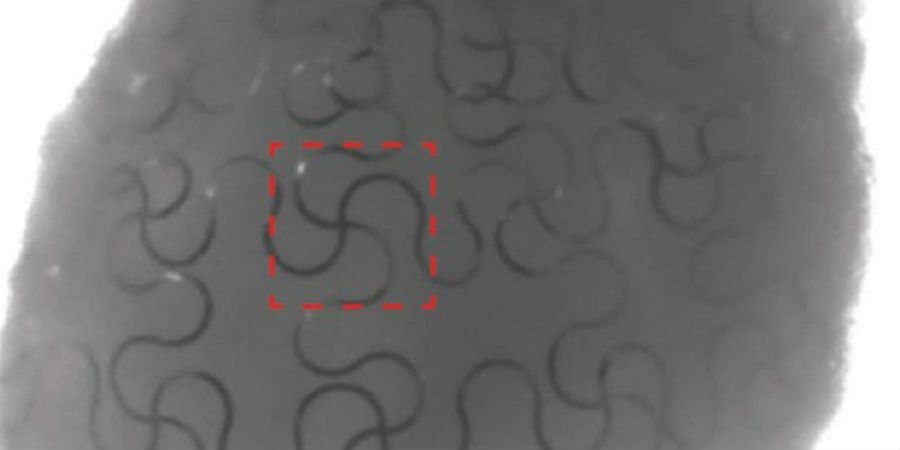

De onderzoekers van de School of Engineering and Applied Sciences (SEAS) van Harvard hebben een manier gevonden om sensors te integreren in mini-organen. Het team maakte eerst een soort rekbaar gaas waarin zeer dunne elektronische draden zijn verwerkt. Het handige aan dit materiaal is dat het zijn bruikbaarheid niet verliest als het wordt uitgerekt; de stof blijft elektronisch actief.

Vervolgens werden vellen van het ‘nanogaas’ op lagen stamcellen (cellen die zich nog tot elk ander celtype kunnen ontwikkelen) geplaatst. Na verloop van tijd groeiden de cellen uit tot driedimensionale orgaanstructuren, met als resultaat cyborganoïden – organoïden met volledig geïntegreerde sensors.

Beeld: Jia Liu/Harvard SEAS